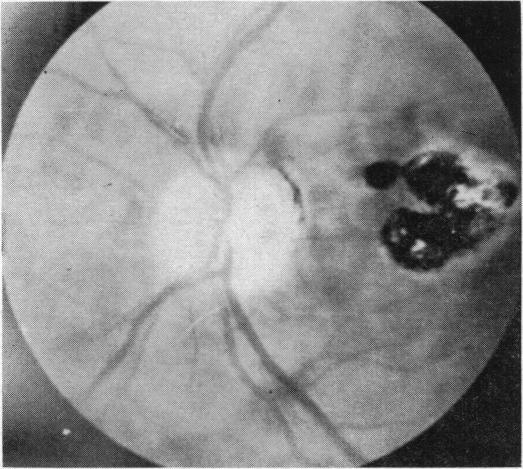

Toxoplasmic retinochoroiditis.